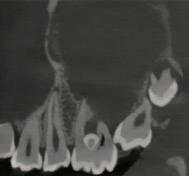

Questions

1. What condition is affecting the first permanent molar in Figure 1?

FIGURE 1: What condition is affecting this first permanent molar?